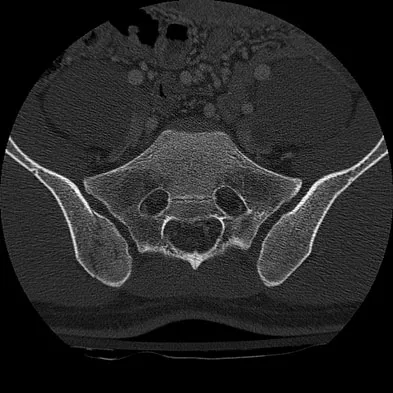

A 58-year-old reports pain and stiffness in his left shoulder following a seizure episode. Diagnosis at the time of the seizure is a frozen shoulder, and management consists of an aggressive physical therapy program of stretching exercises. Four months later he continues to have shoulder pain and has not gained any additional range of motion. A CT scan is shown in Figure 50. Management should now consist of

Explanation